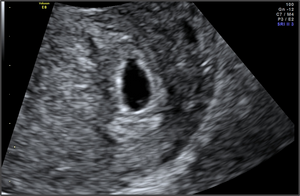

Ultrahangon látható már az 5 hetes embrió?

Hüvelyi ultrahangon még csak a petezsák látható, az embrió még nem. Ilyenkor minden kismama megijed, mikor a vizsgáló orvos azt mondja, hogy nem lát elő magzatot. Azon kívül, hogy a méhen kívüli terhesség kizárható, más értelme nincs ilyen korán vizsgálatra menni. Ennél többet nem fognak tudni mondani.

8-10. héten menj először nőgyógyászhoz. Akkor már képen is fog tudni neked adni a kicsi életről.